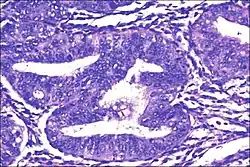

| Micrograph showing simple endometrial hyperplasia, where the gland-to-stroma ratio is preserved but the glands have an irregular shape and/or are dilated. Endometrial biopsy. H&E stain. | |